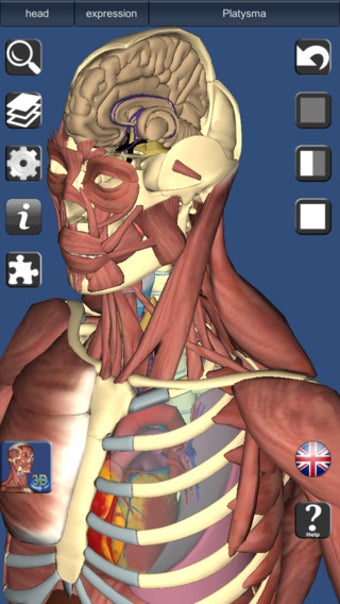

اكتشف جسم الإنسان بشكل ثلاثي الأبعاد

يشبه 3D Anatomy Lite سلسلة Essential Anatomy من التطبيقات من حيث أنه يوفر ميزة ممتازة أداة ثلاثية الأبعاد للمعلمين والطلاب وعشاق الطب العام من أجل استكشاف جسم الإنسان strong>.

على الرغم من أنها لا تبدو رائعة مثل Essential Anatomy ، إلا أنها مفصلة مع القدرة على اعرض النص من أي زاوية strong> بالرغم من أنه يتعين عليك الترقية إلى الإصدار الكامل لمشاهدة كل شيء. p> هناك أيضًا اختبارات ثلاثية الأبعاد strong> لاختبار تكوين معرفتك 3D Anatomy Lite مصدر ممتاز للطلاب. p>